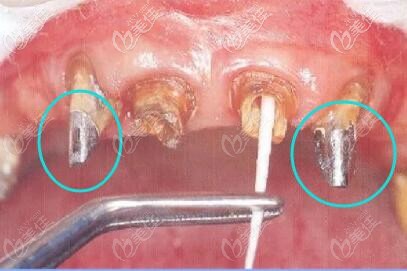

牙齒打樁用金屬好還是纖維好 修復(fù)前先看金屬樁和纖維樁的區(qū)別及優(yōu)缺點介紹 b8709 G0 V0

牙齒打樁,采用纖維樁和金屬樁進(jìn)行修復(fù)有什么區(qū)別呢?小編今天開專題為大家詳細(xì)介紹下兩者的優(yōu)缺點,你就會明白是纖維樁好還是金屬樁好。